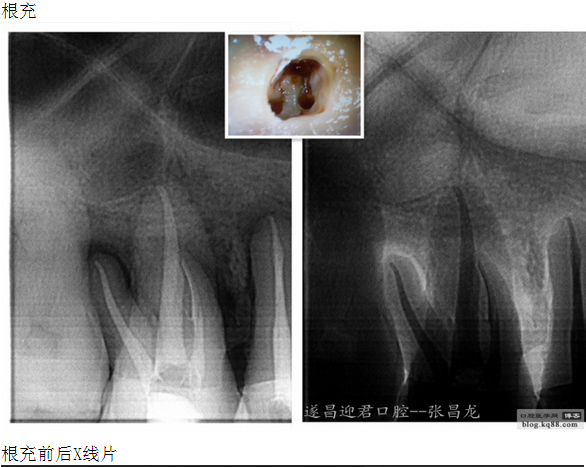

下面是我最近的一個(gè)患者,患者14,15,16均因楔狀缺損導(dǎo)致牙髓壞死,根管治療期間,16的近中頰根發(fā)生了斷針。